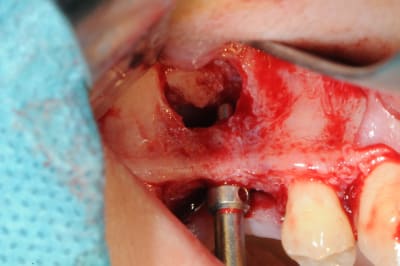

le sujet tombe à pic!

je viens de faire un sinus lift ce matin;

- 3 à 4 mm de hauteur sous sinusienne

- des cloisons de refend partout

- comblement avec du Vital Os

- un implant Axiom D4 L 10

comme je n'avais pas le temps de faire des photos la dernière fois et que j'en étais frustré, je me suis un peu lâcher aujourd'hui...

les premières photos, c'était ouverture par voie latérale

les suivantes;

- forage et transperçage de la crête sans aller trop loin...

- essayage pilier pour parallélisme

- forage à 3mm

- visualisation de la hauteur sous la membrane de Schneider

- utilisation d'un ostéotome diamètre 3.4 puis 3.8

(sous dimensionnement de diamètre par rapport à l'implant prévu :4mm)

- mise en place de l'implant

- séchage discret de la surface osseuse

- injection du Vital Os en palatin et partout autour de l'implant

- hé hé hé ... pas de membrane de recouvrement, le matériaux se suffit à lui même. d'où une petite économie substantielle pour ceux qui ont l'habitude de mettre systématiquement une membrane après un Caldwell-Luc.

- sutures...